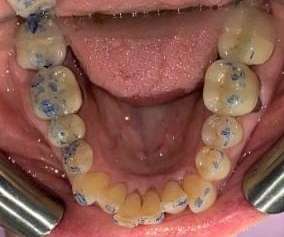

This case combined Invisalign, composite restorations, whitening and veneers to restore damage done from decades of grinding. Most dental offices would have placed crowns on all the back teeth, but with Invisalign treatment to set the bite, we were able to preserve more of the patients teeth while saving time and expense.